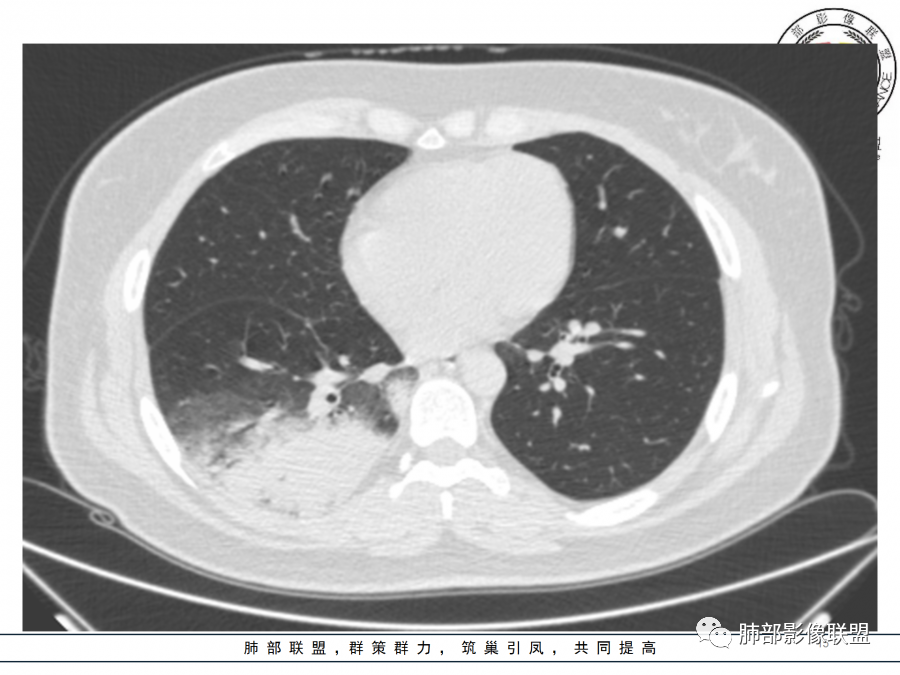

一切∮随缘

右肺胸膜下实变,病变跨多个叶生长,宽基底与胸膜相连,近端支气管穿行病灶内,并可见片状磨玻璃影,边界清,部分远端小支气管堵塞,支气管略有扩张,周围散发小结节,临床年轻女性,炎性指标高,发热六日,首先考虑感染性病变(肺链,奴卡,隐球,OP)鉴别淋巴瘤。

年轻女性,无明显诱因发热,体温略高,起病较急,有畏寒,右下肺紧贴胸膜下片状实变影,部分融合,外围有结节影,性质比较单一,类似于蘑菇兄弟,病灶周围伴有晕,支气管进入近端扩张远端堵塞,常规考虑感染,肺炎链球菌、隐球菌。

青年女性,发热咳嗽5天,炎症标志物升高。右肺下叶大片实变伴周围GGO,GGO内未见细网格,主体与胸膜平行,似多个病灶融合,实变区内见支气管部分进入,部分支气管受压狭窄,周围可见多发卫星病灶。支持炎性,考虑隐球感染,鉴别op。

年轻女性,急性起病,咳嗽,发热,黄痰,白细胞高,CRP基本正常,基础体健。CT提示右肺下叶实变,宽基底与胸膜相连,长轴平行于胸膜,可见支气管充气征,于病变中央截断,走形自然,胸膜下脂肪间隙可见,倾向于隐球菌,鉴别肺链,军团菌等。

年轻患者,右肺下叶大片状实变影,长轴与胸膜平行,内见含气支气管征,周围磨玻璃晕影。考虑感染性病变,隐球?

病灶长轴与胸膜平行,边缘有晕,病灶融合趋势,支气管进入,走行自如,考虑隐球菌肺炎。

年轻女性,急性发病,咳嗽咳痰五天,炎性指标升高,右肺下叶胸膜下大片实变影,周围见磨玻璃影,边界清晰,长轴与胸膜平行,呈融合趋势,支气管进入走行自然,远端截断,考虑炎性,隐球菌可能。

年轻女性,发热,急性发病,白细胞高,右肺下叶大片实变,长轴与胸膜平行,内见支气管走行,远端截断,周围有晕,晕边界清,考虑感染,隐球可能,鉴别淋巴瘤。

年轻女性,右肺下叶胸膜下多发实变、结节影,宽基底与胸膜相连,边缘模糊不清,实变内见支气管穿行,血象高,考虑感染性病变,大叶性肺炎?隐球?

青年女性,发热咳嗽急性起病,右肺下叶大片状实变密度影,长轴平行于胸膜,边缘模糊可见磨玻璃影及高密度结节影,实变内可见支气管穿行,直达病灶远端,考虑感染性病变,隐球菌可能大。

右肺胸膜下实变,病变跨多个叶生长,相互融合,宽基底与胸膜相连,支气管气象,并可见片状磨玻璃影,边界清,炎性指标高,发热六日,考虑感染病变,链球菌?腺病毒待排。

右肺下叶大片状实变影,长轴平行于胸膜,边缘模糊可见磨玻璃影,支气管进入,部分近端阻塞,考虑感染性病变,隐球菌,鉴别大叶性肺炎。

年轻女性,起病急,白细胞,C反高,存在感染。右下肺大片实变影,支气管充气征,长轴平行胸膜,似多个病灶融合,周围GGO,部分清,部分不清。考虑感染,隐球可能。

青年人,右肺多发团片状阴影,边缘模糊,周围可见磨玻璃影,内部有支气管空气征,考虑感染性病变,隐球菌感染可能。

右肺下叶大片状实变影,从外向内,长轴平行于胸膜,边缘模糊,可见磨玻璃影,支气管进入,远端部分阻塞,考虑感染性病变,隐球菌,鉴别淋巴瘤。

26岁,女性,发热、咳嗽5天。咳少量黄痰,起病急,病程短,白细胞及中性高,血沉及D-二聚体增高。胸部CT:右肺下叶大片实变,长轴沿胸膜分布,宽基底与胸膜接触,边界不清,周围GGO,部分团片影融合,病灶内可见支气管充气征,部分支气管进入病灶后阻塞。考虑:感染性病变,隐球菌?脓毒肺栓塞?鉴别:肺炎型肺Ca。

年轻女性,右肺下叶一大片实变影,似有多个结节影融合,周围有晕,内见支气管充气征,部分支气管进入后截断,病变近胸膜,长轴胸膜平行,考虑炎性,隐球菌首先考虑。

青年女性,影像表现右肺下叶胸膜下大片状实变影,近端见充气支气管征,边缘见片状磨玻璃影,下叶背段尚可见一结节。考虑感染性病变,隐球菌感染可能。

右下肺大片实变影,空气支气管征,边缘GGO,小叶间隔增厚,周围有蘑菇兄弟,基底宽,与胸膜平行,考虑隐球菌感染,鉴别肺炎型肺癌。

晨读:年轻女性,右肺胸膜下实变影,平行于胸膜,边缘磨玻璃影,内见支气管充气征,走形自然,略扩张。考虑感染性改变,隐球,肺链。2月发病,病毒性肺炎要考虑。鉴别淋巴瘤。

晨读:年轻女性,发热咳嗽5天。白细胞计数升高。右肺下叶大片状高密度影,边缘模糊,有实变 GGO,其内见支气管气相、无受压变细,无枯枝表现,其近端支气管无异常,右肺下叶背段见结节状影,定性考虑:炎症,隐球菌感染可能,炎症型肺癌不支持。

右下肺胸膜下大片状高密度影,其长轴与胸膜平行,病灶近端GGO模糊,部分支气管进入后阻断,支持感染性病变,考虑隐球菌